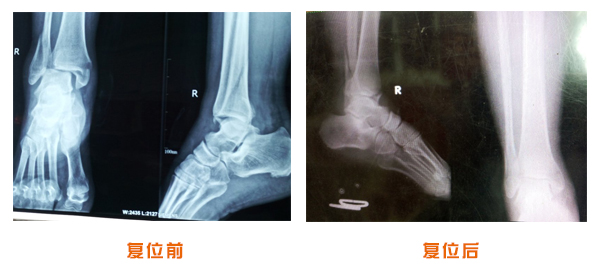

肥城市安駕莊梁氏骨科醫(yī)院是一所以梁氏手法正骨配合膏藥為特色的現(xiàn)代化專科醫(yī)院。

梁氏骨科術始創(chuàng)于清雍正年間,歷經(jīng)八代,至今已有三百年歷史。據(jù)1929年泰安縣志載“梁瑞圖先生,字增生,號蓮峰,安駕莊人,精岐黃并發(fā)明接骨,凡跌打車凡跌打車軋皮不破而碎骨者......【詳細】 |